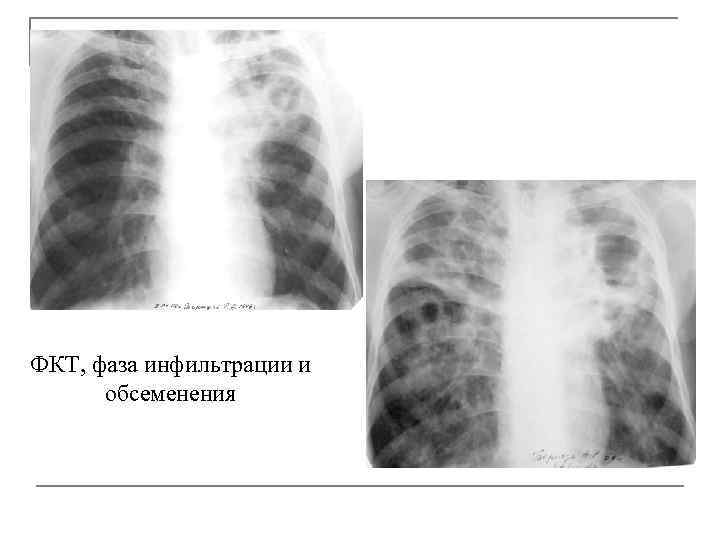

Симптомы и лечение инфильтративного туберкулеза легких

Раздел: Снимки-откровения